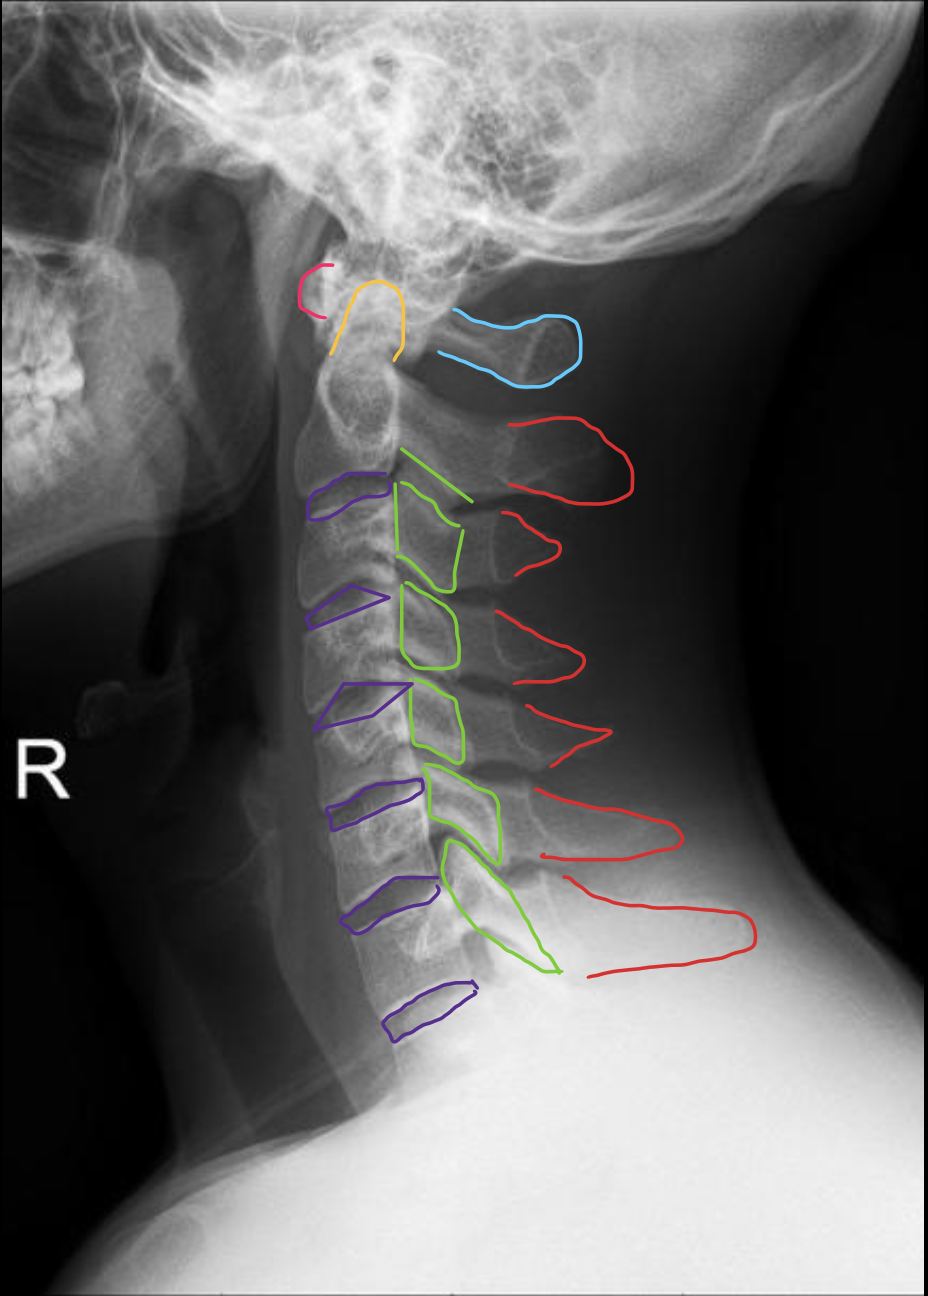

寰椎前弓

Anterior arch of C1

椎板棘突线(椎弓后缘线)

Spinolaminar

棘突后缘线

Posterior spinous

椎体

Vertebral body

椎板

Lamina

关节突关节

Zygapophyseal joint

椎间盘

IVD (Intervertebral Disc)

分叉棘突

Bifid Spinous process